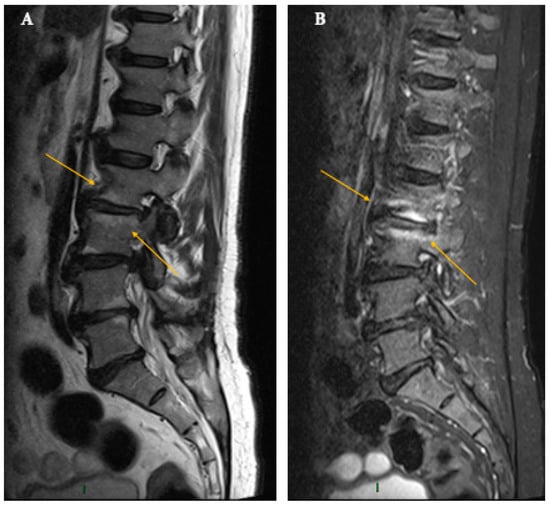

5. Tuberculous Origin (Pott’s Disease)

6. Brucellar Origin